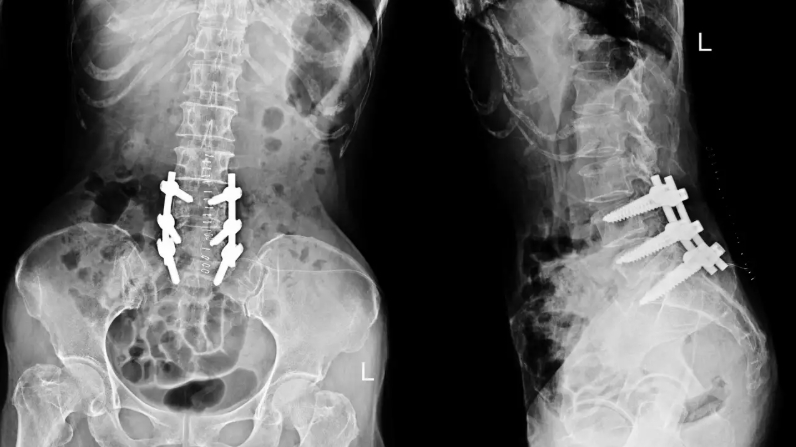

According to the findings shared by Minimally Invasive Neurosurgery of Texas, patients undergoing laminectomy through advanced spine surgery Plano TX techniques often experience reduced postoperative discomfort and faster mobilization compared to traditional surgical approaches. By using refined instrumentation, high-resolution imaging, and muscle-sparing methods, surgeons are able to preserve spinal integrity while effectively relieving pressure on affected nerves.

The press release further explains that advanced spine surgery Plano TX enables greater precision during laminectomy procedures, which is essential when treating complex spinal anatomy. This level of accuracy helps lower the risk of complications, supports better alignment, and contributes to improved functional outcomes. Minimally Invasive Neurosurgery of Texas reports that these advancements are especially beneficial for patients who require surgical intervention but are concerned about recovery time and long-term mobility.